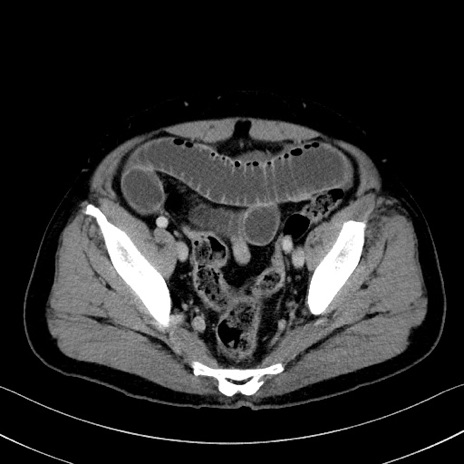

症例35(横断像)

【症例】70歳代 男性

【主訴】腹部膨満、嘔吐

【現病歴】昨日より腹部膨満感出現。本日増悪し、仙痛出現。嘔吐あり、受診。

【既往歴】糖尿病、胆摘後

【身体所見】BP 149/80mmHg、HR 74/min、BT 35.9℃、腹部:膨満、軟、圧痛なし。腸雑音減弱あり。上腹部正中切開瘢痕あり。

【データ】WBC 13500、CRP 1.72